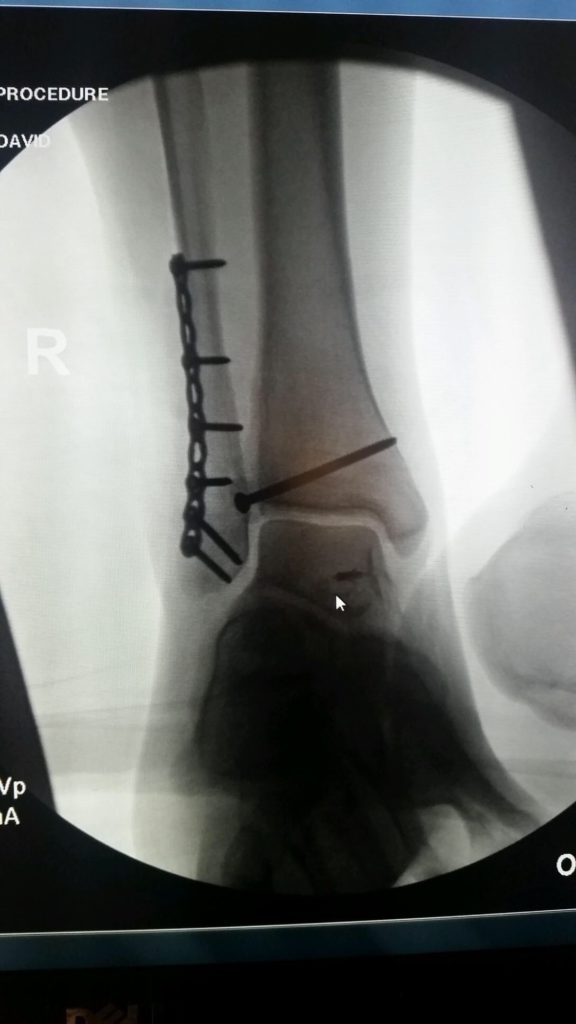

In October 2016 I was knocked over during a night out in New York City and dislocated and fractured my ankle. The following week, I went to HSS and met with Dr. Wellman. Right away he was very positive and optimistic with my options. He was able to fit me into his schedule four days later (10/24/2016) and inserted eight screws and a plate into my ankle. I have been going to PT at HSS for the past three months, seeing Erica Fritz. One month after surgery I was walking on my own without a boot or crutches. I am now able to walk and run without any pain! Thanks to everyone at HSS that has helped be get back on my feet so quickly!